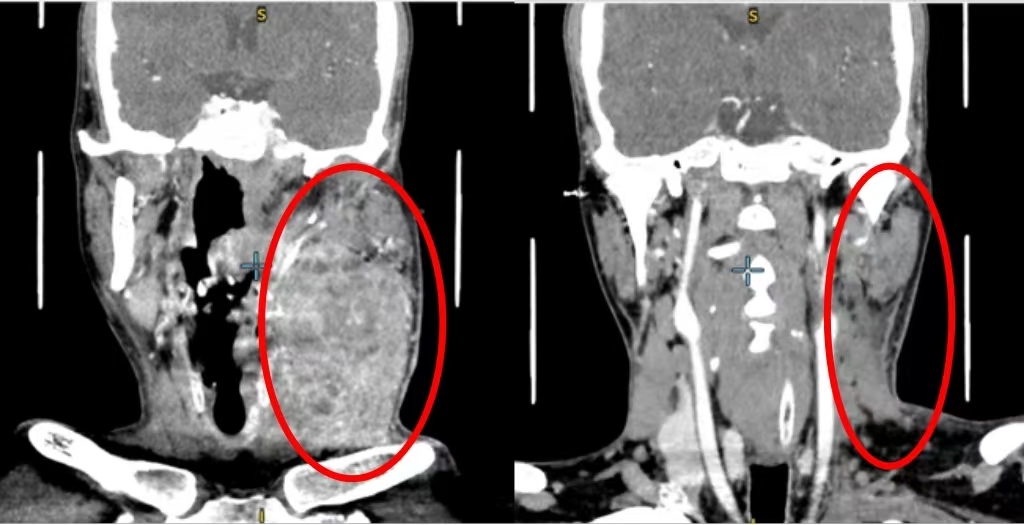

这名33岁患者的影像检查线上,肿瘤病灶从舌头转移到了颈部。